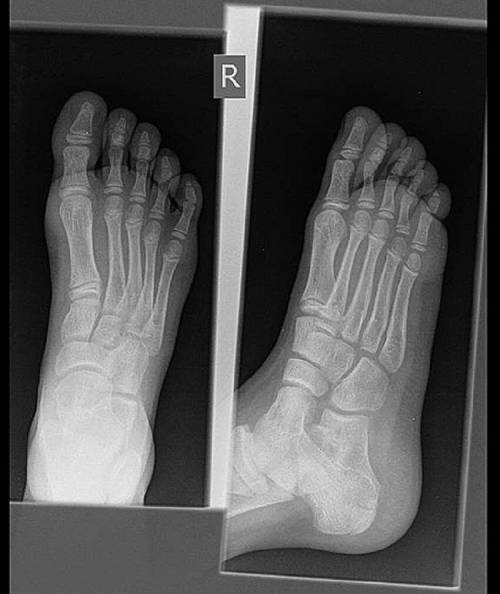

نقرس (Gout)

آقای ۳۵ ساله

بیا این عکس رو بگیر :

_right foot xray AP&Lateral

👩🏻⚕️ خب گرافی شما نرماله

شدت دردت خیلی زیاد هست شاید علت دردت چیز دیگه ای هست

جواب آزمایشات درخواستی نرمال بجز اوریک اسید بالا